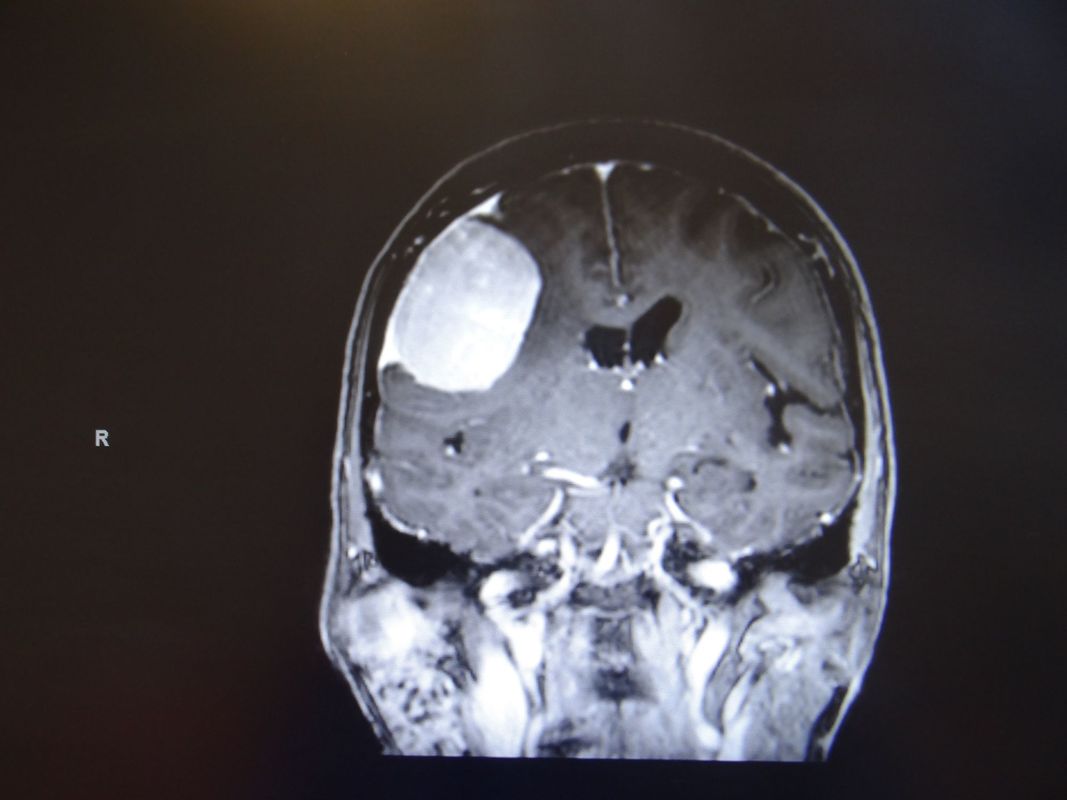

On distingue deux types de tumeurs cérébrales. La première catégorie englobe les tumeurs dites primaires, dont l’origine provient des cellules du cerveau (astrocytes, oligodendrocytes, neurones, cellules épendymaires, cellules méningées). La deuxième catégorie comporte les tumeurs dites secondaires, qu’on appelle plus communément les métastases. Ce sont des tumeurs provenant d’un cancer localisé sur un autre organe du corps. En effet, ces dernières ont la propension de migrer et former une métastase dans le cerveau.

Les tumeurs primaires du cerveau sont divisées en deux sous-catégories : les tumeurs dites intra-axiales, c’est-à-dire qu’elles proviennent des cellules du cerveau (gliomes, épendymomes, neurocytomes,..) et les tumeurs extra-axiales, dont l’origine provient des cellules à l’extérieur du cerveau (méningiome, schwannome,…)

​En général, les tumeurs peuvent être traitées par une craniotomie avec chirurgie d’exérèse et /ou une biopsie quand la localisation ne se trouve pas dans une région profonde du cerveau ou dans une zone « sensible » que l’on nomme fonctionnelle. Le traitement comporte également, dans beaucoup de cas, une radiothérapie et/ou une chimiothérapie.